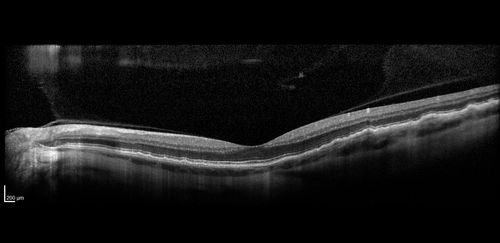

Late Onset Retinal Degeneration (L-ORD)

55 year old with acute vision loss from a CNVM in the right eye. He responded to Lucentis therapy. His mother and her family has been confirmed genetically to have L-ORD and were part of the early reports.